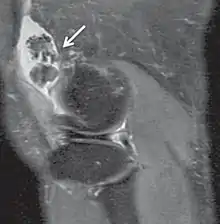

In the early stages of the disease it is often confused with tendinosis and/or arthritis. Once it reaches transitional the loose bodies become apparent with X-ray in greater than 70% of cases, with MRI often showing where xray fails. In experienced hands, ultrasound is also useful for the diagnosis.[2]

Rare and little known, with currently no known cure, the disease gradually forms blisters in the thin flexible membrane of the synovium, which calcify and enlarge. These nodules eventually break free and float around the joint space becoming larger – these add to the discomfort and stiffness of the joint. The affected tissue will show up as a semi-solid mass in an MRI scan, final diagnosis is usually confirmed by taking a biopsy. The disease generally affects only one of the larger weight bearing joints (hip, ankle, knee) – although the elbow, and wrist can also be affected. It rarely involves the temporomandibular joint (TMJ) and most publications are case reports.[3]

Diagnosis is by medical imaging; X-ray, CT scan and MRI.[1] For diagnosis of the TMJ, Cone beam computed tomography (CBCT) can also be useful.[6]